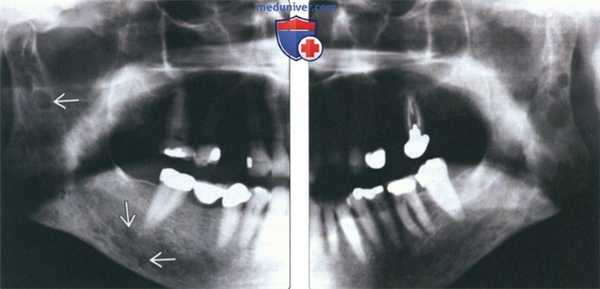

(Слева) На панорамной рентгенограмме у мужчины 80 лет с ранее не выявленной множественной миеломой визуализируются множественные хорошо отграниченные («выштампованные») просветления в ветви и теле нижней челюсти справа.

(Справа) На панорамной рентгенограмме у этого же пациента определяются аналогичные очаги в нижней челюсти слева. У 20-30% пациентов с множественной миеломой возникает поражение челюстей, которое, однако, редко становится первым проявлением заболевания.